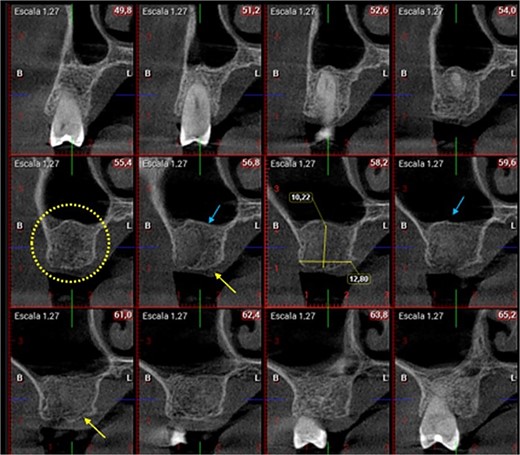

A control appointment was made 8 days later, and the scar tissue with slight erythema on the edges of the alveolus was observed (Fig. 6). The patient was asymptomatic, and the membrane was in position to cover the entire alveolus. After the fourth week, granulation tissue was observed covering almost the entire alveolus, and an area was observed where the membrane found below this granulation tissue could be seen (Fig. 7). About 3 months after surgery, healed soft tissue was observed, and a CT scan was requested, where the maxillary sinus was observed without evidence of pathologies and hypodense alveolar bone compatible with immature bone in the process of calcification (Fig. 8). After 6 months, keratinized tissue and a completely healed alveolus were observed (Fig. 9), and cone beam computed tomography (CBCT) was requested to evaluate the results and see the possibility of placing an implant. In the CT scan, continuous sinus and alveolar cortex were observed with an image compatible with bone in the healing process (Fig. 10).